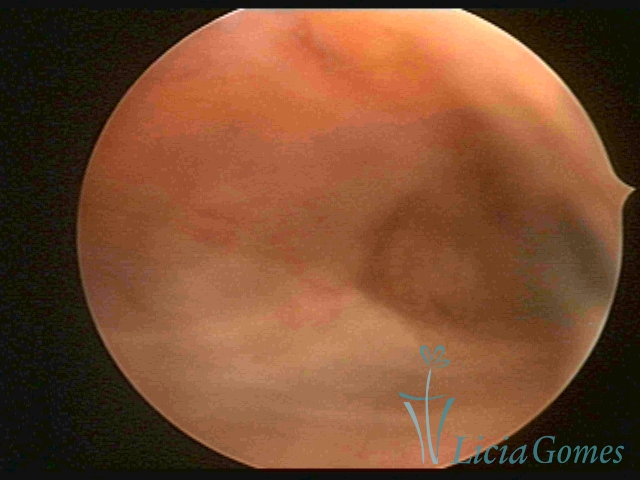

Second part or middle section

In the middle section of the cervical canal, the details of the buds are lost. It is possible to view creases and crypts. Longitudinal grooves are frequently observed. They are the most compact tissues presenting the most vascularized surface, whose vessels follow its passageway.